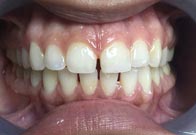

(4) Diastema Closure

Before Treatment

After Treatment

Patient with a complaint of a gap in between upper central incisors. Dental Veneers done to close the gap between the central incisors